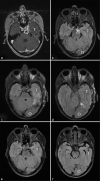

Figure 2:

Preoperative magnetic resonance imaging (MRI); a: T1 + gadolinium, b: T2-fluid-attenuated inversion recovery (FLAIR), and asterisk: clival meningioma. Postoperative MRI, c and d, day 3, e, and f 1 year; T2-FLAIR. T: Temporal lobe. O: Occipital lobe.